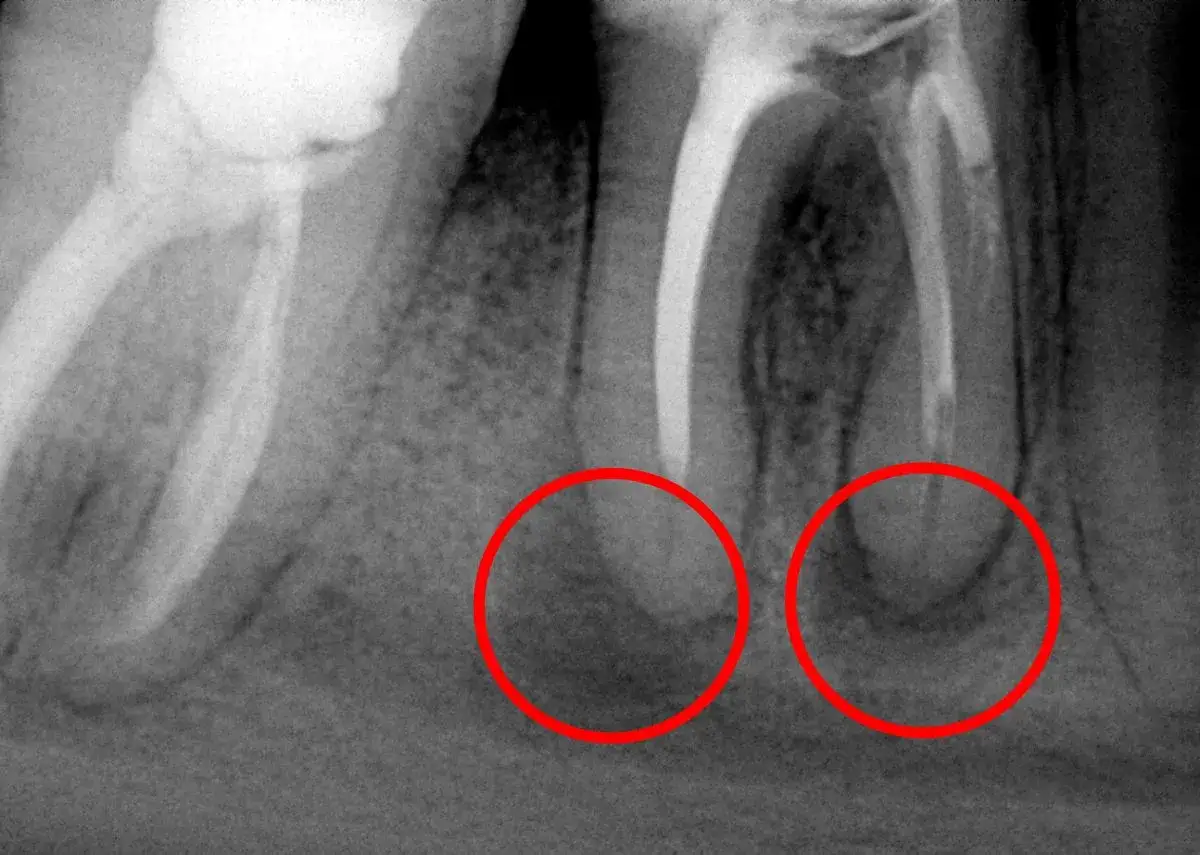

Obrazowanie radiologiczne jest nieodzownym elementem diagnostyki torbieli. Zaczynamy od RTG punktowego, które pozwala szczegółowo ocenić pojedynczy ząb i jego okolicę, uwidaczniając niewielkie zmiany okołowierzchołkowe. Jeśli potrzebna jest szersza perspektywa, wykonujemy pantomogram, czyli zdjęcie panoramiczne, które daje ogólny obraz stanu całego uzębienia, obu szczęk i zatok, co jest przydatne do wykrywania większych zmian. Jednak w przypadku dużych lub trudno położonych torbieli, a także gdy chcemy precyzyjnie określić ich rozmiar, lokalizację i stosunek do sąsiednich struktur, takich jak zatoki szczękowe, kanał żuchwy czy nerwy, niezastąpiona staje się tomografia stożkowa (CBCT). To badanie dostarcza trójwymiarowego obrazu, który pozwala na dokładne zaplanowanie leczenia i minimalizację ryzyka powikłań.

Chociaż badania radiologiczne są niezwykle pomocne, muszę podkreślić, że sam obraz na zdjęciu nie pozwala na pewne odróżnienie torbieli od innych zmian, takich jak ziarniniaki okołowierzchołkowe czy blizny kostne, które mogą wyglądać podobnie. Właśnie dlatego, zgodnie z wytycznymi, ostateczne rozpoznanie torbieli korzeniowej zawsze wymaga badania histopatologicznego usuniętego materiału. Oznacza to, że po chirurgicznym usunięciu zmiany, pobrany fragment tkanki jest wysyłany do laboratorium, gdzie patolog pod mikroskopem ocenia jego strukturę komórkową. Jest to kluczowe dla potwierdzenia diagnozy i, co równie ważne, wykluczenia innych patologii, w tym zmian nowotworowych. Według danych StatPearls, badanie histopatologiczne jest złotym standardem w diagnostyce torbieli zębopochodnych, zapewniając precyzyjne rozpoznanie.